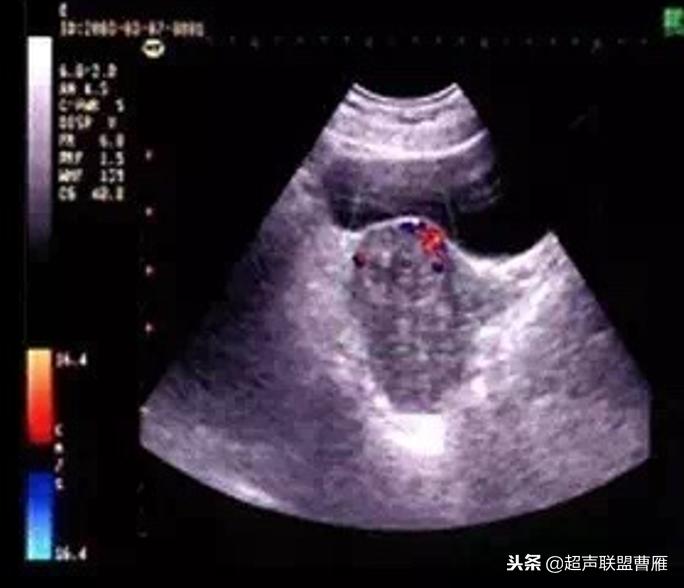

1.子宫下段见完整妊娠囊,见胎心搏动,见扩张血管及多量血池

2.孕囊周围局部肌层血流信号丰富,可记录到类滋养层周围血流频谱

(I型胚胎存活型)